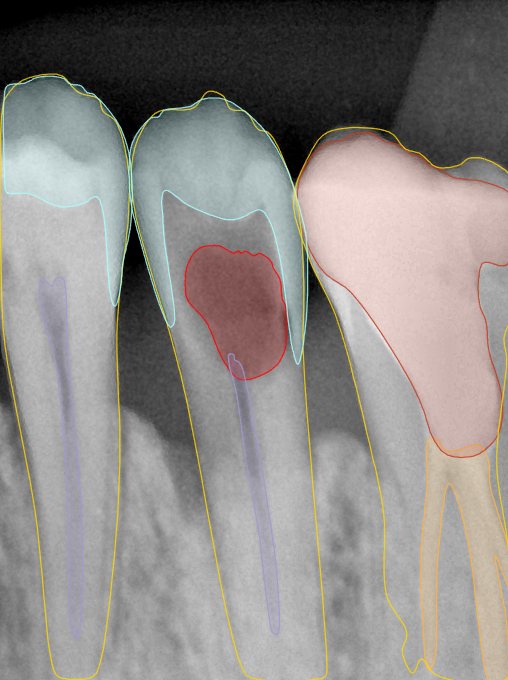

第二版算法问题测试

| 第一版 | 第二版 | 是否解决 | |

|---|---|---|---|

![]() | ![]() ![]() 边角识别有问题 龋齿识别不全 牙髓识别不全 | ![]() | 解决 |

![]() | ![]() 边角识别有问题 识别信息有误 自查(牙冠识别不全) | ![]() | 解决 |

![]() | ![]() ![]() 边角识别有误 大范围填充识别遗漏 | ![]() | 解决 |

![]() | ![]() 识别信息不全 | ![]() | 解决 |

![]() | ![]() ![]() 边角问题 牙胶识别不全 牙冠识别不全 | ![]() | 解决 |

![]() 换图片 | ![]() | ![]() 牙冠部分稍微白了一些就识别成小范围修补,部分判断异常 | 部分解决,修复类略敏感,牙冠部分稍微白了一些就识别成小范围修补,部分判断异常。 |

![]() | ![]() ![]() 牙冠识别不全 牙髓不全 根尖炎龋齿识别有误 | ![]() | 解决 |

![]() | ![]() | ![]() | 解决 |

![]() 换图片 | ![]() | ![]() | 解决 |

![]() | ![]() 牙冠识别有误 | ![]() | 解决 |

![]() 换图片 | ![]() ![]() 边角识别有误 | ![]() 修复类敏感 | 部分解决,图像过白,导致修复类判断异常。 |

![]() 换图片 | ![]() 牙冠识别不全 | ![]() 修复类敏感 | 部分解决,图像过白,导致修复类判断异常 |

结论:修复类出现了不鲁棒的情况,后续需要加入轮廓的扩充数据进行增强。